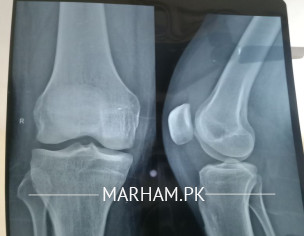

Salam Hi Mujhy Qamar aur Tang ma kichao hwa us ke bad Beth Ker Namaz parhi Jis Ki wajha sa ghutnay pa ziyada Zor para to Phir Ghutna Sooj Geya aur Kafi pain ha Tang Fold he nae horahe washroom ma commode use kerna par Raha ha Qamar ke patho ma bhe kichao horaha ha thora thora checkup bhe kerwaya ha Lakin farq nae para ghalti ye hwe ke Aik Hakeem Ki medicine kha Li us Ny jisem ma kushki kichao Ker di us Hakeem na kha tha ye medicine Body ma Sardi Khuski Paida Karti ha Fish Oil capsules bhe khaye Hain Milk ma Desi Ghee bhe Dal Ker Piya ha Phir bhe Aram nae Aya Please Help Baki koi masla nae ha Na Blood Pressure na Sugar ha JazakAllah

Attach Photo here: